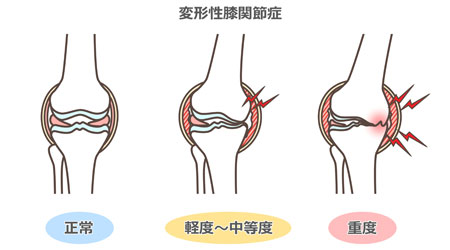

変形性膝関節症とはなにか

まず、変形性膝関節症とはなにか簡単に見ていきましょう。

変形性膝関節症は、加齢とともに膝の関節内にある半月板や軟骨の老化が進み、少しずつすり減っていくことで発症します。

それにより膝の動きが制限されていったり、関節内に慢性的な炎症が起きている場合は痛みを出したり、ひどい場合は水が溜まる方もいらっしゃいます。

高齢者に多い疾患で80代が最も多い変形性膝関節症ですが、早いと40代で発症する場合もあります。

男女比は1:4で、女性の方が男性の4倍の発症率であると言われています。

変形が進んでいくと、膝がO脚のように変形していくのも特徴の1つです。